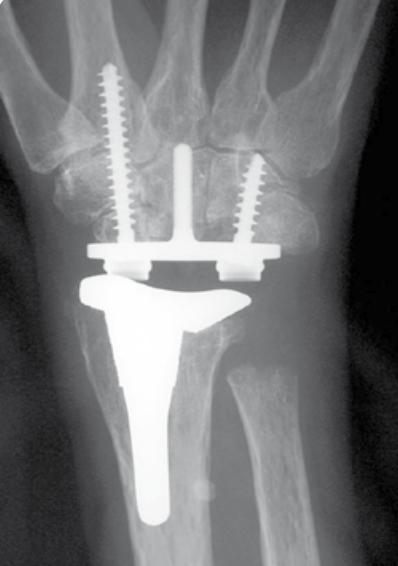

Total wrist arthroplasty

Indications

Low demand patient

Intact wrist extensors

Good bone stock

Technique

TWA

- uncemented radial prosthesis

- excise lunate and apply carpal cutting block to capitate

- cut 1 mm hamate / capitate head / midscaphoid

- screw fixation of carpal plate

- trial polyethylene component

Results

- 425 primary total wrist arthroplasty followed for mean 2 years

- 90% inflammatory arthritis

- intra-operative fractures 2%

- postoperative fractures 2%

- 88% 10 year survival